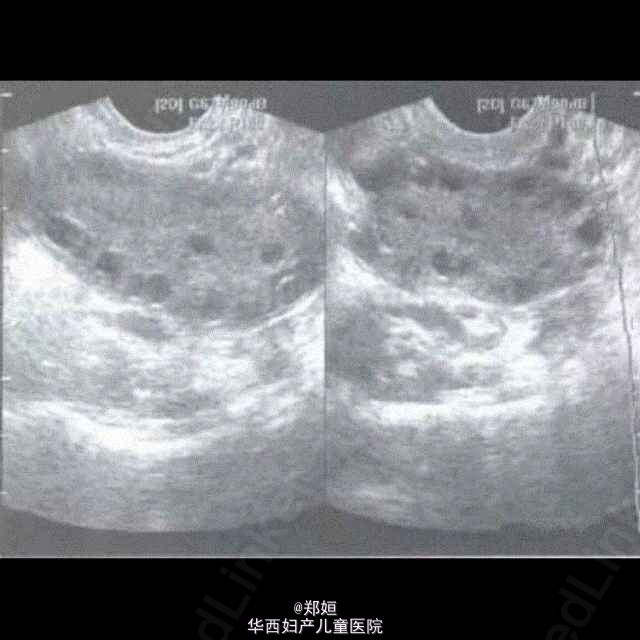

多囊卵巢综合征的超声诊断

PCOS是调节机制失常所产生的一种综合征,患者具有月经稀发或闭经、不孕、多毛和肥胖等一组症状,双侧卵巢呈多囊性增大改变。这有几个很好的超声诊断图跟大家分享一下吧。